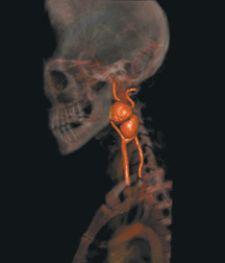

10) 3-D Surgery. Surgeons have traditionally relied on 2-D X-rays to view affected areas before surgery, and on invasive techniques to locate hard-to-reach tumors or damaged organs once in the operating room. Image-guided surgery uses CT scans, MRI and light emitting diode cameras to create 3-D real-time images of the surgical field and the precise location of tumors.

Image-guided surgery has many applications and is particularly useful to neurosurgeons in their preoperative assessments for brain tumor surgery where surgeons can more confidently remove brain tumors without causing new injuries to delicate structures.